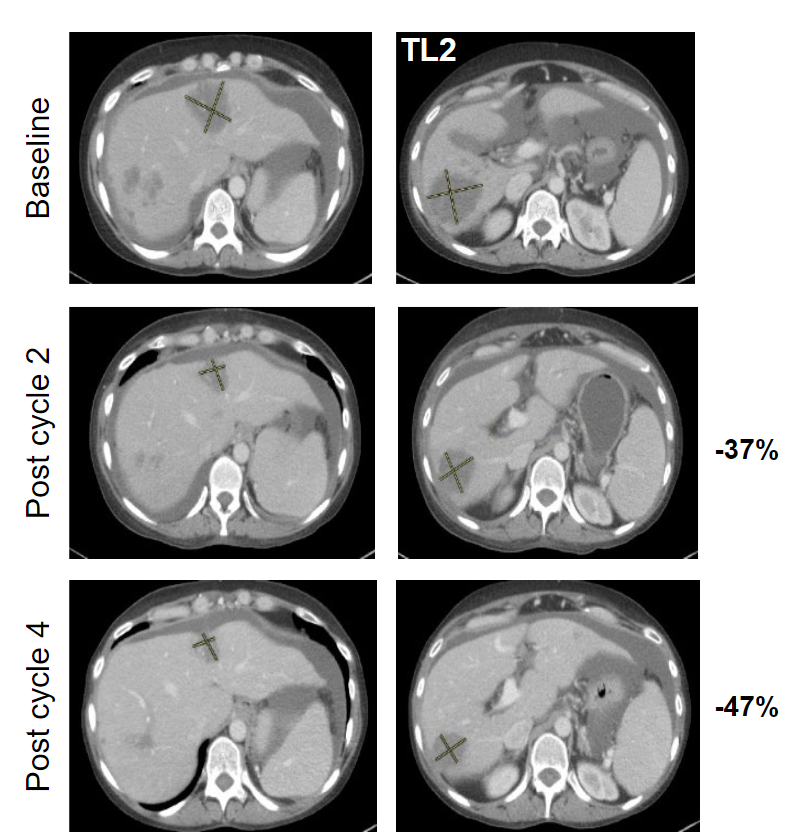

KRASG12C靶向药Adagrasib(MRTX849)治疗结直肠癌患者的肿瘤缩小近50% 结直肠癌

结直肠癌KRASG12C靶向药Adagrasib(MRTX849)治疗结直肠癌患者的肿瘤缩小近50%

KRASG12C靶向药Adagrasib(MRTX849)治疗结直肠癌患者的肿瘤缩小近50%在一项临床实验中,所有KRAS g12c肠癌患者在接受了一款全新的靶向药物治疗后,肿瘤均有不同程度的缩小!好消息是,这款药物已在中国获批开展临床试验,国内的患者也可以申请啦!结直肠癌全身转移,一款新药让肿瘤缩小近50%美国47岁的M大婶在确诊左侧的结肠腺癌时已经是晚期